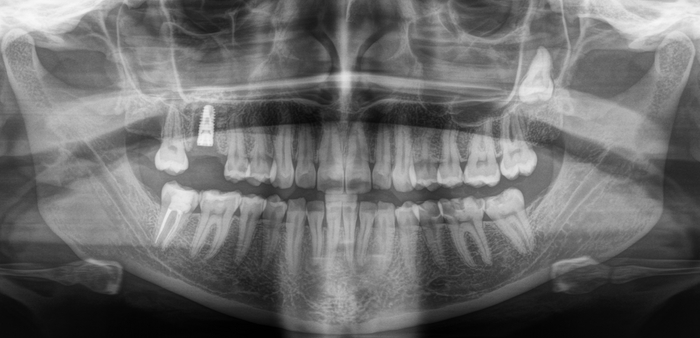

На панорамном снимке, сделанном после имплантации, хорошо видно, насколько высоко и неудачно она располагается:

Вжух и год позади:

В целом, каких-то явных изменений нет. В подтверждение тому, что это не один и тот же снимок, вы можете обратить внимание, что на имплантате уже установлена постоянная коронка.

Добрый вечер… А что это значит?... Прекрасно видно, что фолликулярная киста начала расти и оттеснять зуб мудрости дальше в пазуху, что несколько затрудняет его удаление. Блять, подумал я, надо было сразу удалять.

Контрольный снимок после удаления: